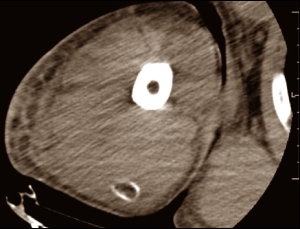

Vitamin D3 is needed for the deposition of calcium in bones. But an overdose of vitamin D3 has the opposite effect, extracting calcium from the bones, increasing the amount of calcium in the bloodstream and resulting in it being deposited in places you don't want it to be deposited. That explains the scar tissue that the Brazilians found in the bodybuilder's kidneys – the result of calcium being deposited there [black patch in the photo below] and damaging part of this organ.

The researchers also found calcium deposits in the upper arms and pectorals of the bodybuilder. These were the places where the man had injected himself with vitamin D oil. Below is a picture of one of the depositions in his upper arm [at the bottom of the scan].